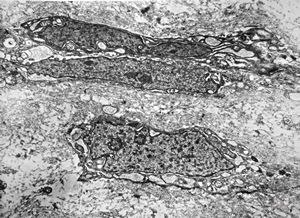

F,25y. | myopathy - atrophic and regenerating muscle cells